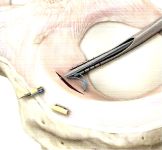

Artroskopie kolenního kloubu

- Náhrada PZV (předního zkříženého vazu) šlachou m. semidentdinosus a m. gracilis, BPB autoštěpem a BPB alloštěpem.

- Náhrada VPV (vnitřního postranního vazu) šlachou m. semitendinosus a m. gracilis

- Náhrada ZPV (zevního postranního vazu) a posterolaterálního komplexu šlachou m. semitendinosus a m. gracilis